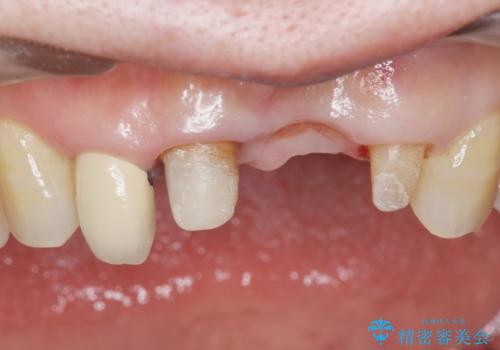

前歯が抜けそう ブリッジできれいに 70代女性

- 上下の前歯が抜けそうだとのことで来院されました。

精査したところ、動揺の著しい上下の前歯は重度の歯周病により保存不可能と判断しました。

ブリッジ、インプラント、義歯の選択肢の中で上下前歯ともにブリッジをご希望されました。

抜歯後歯肉の治癒を十分に待ったのち、ブリッジによる補綴治療を行いました。

歯周病が重度であったため抜歯後の歯肉の陥凹が大きく、GBRや歯肉移植による歯周組織の再建をおすすめしましたが、ご希望されませんでした。